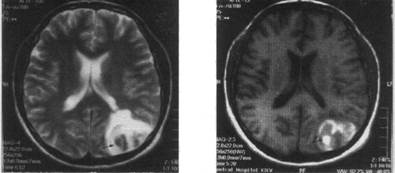

Острый ишемический территориальный инфаркт в бассейне правой внутренней сонной артерии (исследование выполнено через 47 ч от начала заболевания):

а - МРТ головного мозга (аксиальная плоскость, срез на уровне полушарий мозга, Т2 TIPM-взвешенное изображение): визуализируется большой гиперинтенсивный очаг ин­фаркта, занимающий все правое полушарие большого мозга и переднюю часть лобной области противоположного полушария (показано стрелкой); б - МРА магистральных со­судов головного мозга: выявлена окклюзия правой внутренней сонной артерии, о чем сви­детельствует отсутствие MP-сигнала (показано тонкой стрелкой), левая внутренняя сонная артерия определяется четко (показано толстой стрелкой)